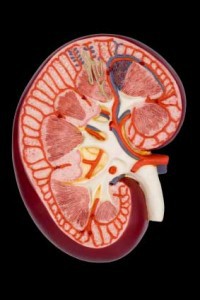

Most people are born with two, healthy functioning kidneys. The kidney, part of the urinary system, is an organ located in the body’s midsection on either side of the spine. There is one kidney on both the left and right side of your body.

Its name is representative of its shape, as the shape has been described as having the same shape as a kidney bean. However, unlike a kidney bean, on the inside of the kidney organ is a complex filtration system that serves to remove toxins from the bloodstream and eliminate them from the body in the form of urine.

Its name is representative of its shape, as the shape has been described as having the same shape as a kidney bean. However, unlike a kidney bean, on the inside of the kidney organ is a complex filtration system that serves to remove toxins from the bloodstream and eliminate them from the body in the form of urine.

So, the kidney on one end receives blood, and the blood travels through the many filters of the kidney. As blood passes through each level of filtration it becomes clean and returns to give oxygen and energy to other organs in the body. This filtration system also helps to regulate the amount of sodium and potassium in your body; secretes a hormone that signals the body to make more red blood cells; as well as maintains blood pressure.

Finally, the toxins that are filtered out of this blood are removed from the body as urine. The urine leaves the kidney (with its waste) through tubes called ureters that open into the bladder. Then, as the bladder fills, urine is released from the body through another small tube called the urethra.